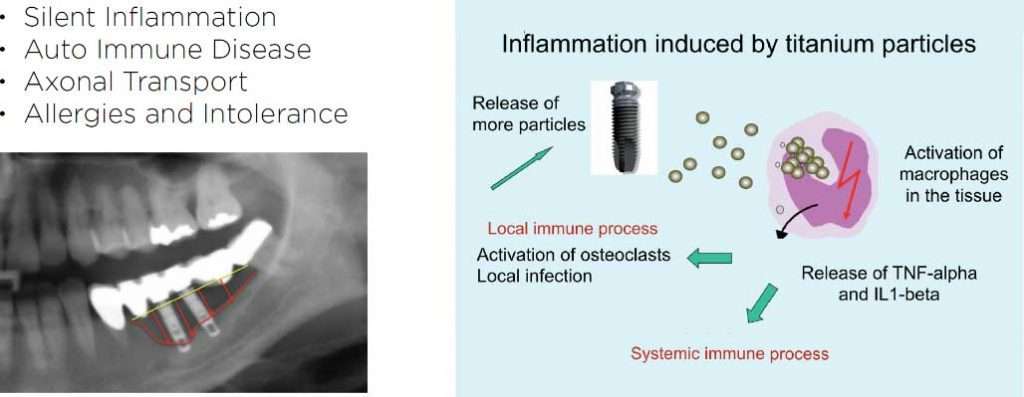

Silent inflammation due to root canal therapy, cavitation (avascular osteonecrosis) and titanium implants leads to immune system activation. The intraoral interference fields created by metals, NICOs, bacteria in root canal treated teeth produce highly toxic hydrogen sulfides (Thioether/Mercaptan), metals show cytotoxic, immunological and carcinogenic effects and NICOs (Neuralgia inducing osteonecrosis) consist of increased inflammatory mediators like RANTES, FGF-2 and IL-1ra.

A change in mindset is urgently required, as there are unfortunately certain factors in our environment that pose a progressively intensive risk to our health: increasing electromagnetic radiation in the form of high gigahertz frequencies related to mobile communications, WLAN and DECT technology. Also, the addition of titanium oxide (E171) to cosmetics, sun screen, oral contraceptives, toothpaste, chewing gum and even yogurt has led to an increasing intolerance to titanium, which is still being used in alternative medicine and traumatology. Yet even in its purest form ‘Grade 1 titanium’, this chemical element still contains up to 0.20 % iron and traces of nickel as well. This is an alarming fact when you consider that 80% of women in Europe experience an allergic reaction to nickel. More significant risk factors present the intraoral interference fields.